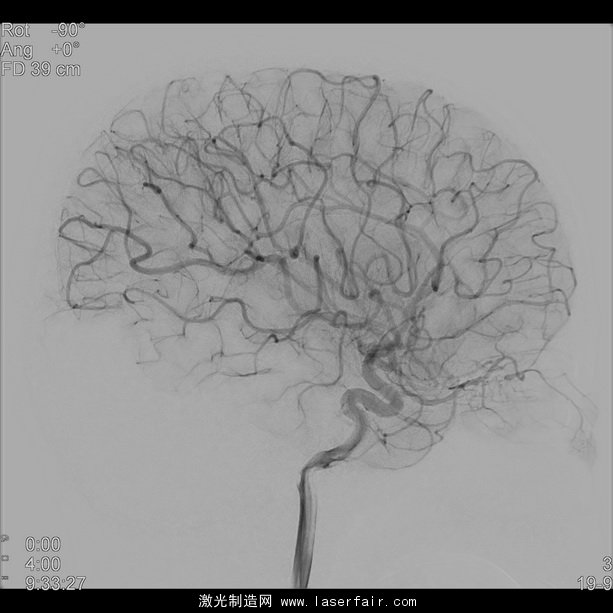

為應(yīng)對(duì)這些困難,飛利浦的 NeuroSuite 包含一個(gè)雙面介入式 X 射線系統(tǒng),并獨(dú)家整合了兩款新探測(cè)器:飛利浦前額 FD20探測(cè)器提供實(shí)時(shí)的2D 和3D 影像以實(shí)現(xiàn)實(shí)時(shí)導(dǎo)航和即時(shí)療法反饋;小型側(cè)面 FD15探測(cè)器可放置于遠(yuǎn)離雙肩和非??拷^部的部位。這樣的更短距離和獨(dú)特的探測(cè)器結(jié)合,能以更少的 X 射線劑量提供清晰的全腦影像,以及對(duì)神經(jīng)與脊椎介入進(jìn)行了優(yōu)化的3D 影像。

卡羅林斯卡大學(xué)醫(yī)院神經(jīng)放射科副主任醫(yī)師、神經(jīng)造影和立體定向主管 Michael Soderman 醫(yī)師說:“血管造影術(shù)系統(tǒng)在介入式神經(jīng)放射科的表現(xiàn)對(duì)患者的安全極為重要。飛利浦的最新創(chuàng)新是在額狀面有著20英寸新探測(cè)器的 NeuroSuite,能提供極好的3D 影像和足夠大的脊椎影像。側(cè)面則有15英寸的新探測(cè)器能提供完整的大腦血管影像,可減少碰撞危險(xiǎn)并促進(jìn)投影自由。”

NeuroSuite 的中心是將放射劑量減少了73%且不犧牲影像品質(zhì)[2],[3]的飛利浦 AlluraClarity,以及在血管背景和血管組織直至穿支血管中可視化顱內(nèi)設(shè)備[1]的VasoCT。